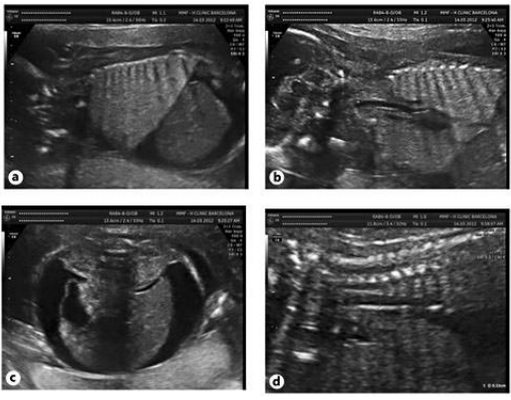

Последний, 7 случай был у женщины 38 лет, которая беременна впервые без тягостного акушерско-гинекологического анамнеза. Сканирование в первом триместре было нормальным и комбинированный скрининг также показал низкий уровень риска хромосомных аномалий. Диагноз ВОДП был обнаружен на сроке беременности 21 неделя за счет генерализованного отека кожи в 15 мм и асцита у плода (рис.3). На УЗИ визуализация трахеи была нормальной, диаметром в 3 мм. Кроме того, наблюдаем нормальный вид голосовых связок, которые периодически двигались в просвет гортани (рис.4). Тем не менее, ни одного движения жидкости через трахею при допплеровском сканировании не удалось обнаружить. Полное сканирование плода с помощью ультразвука и магнитно-резонансной томографии исключило другие сопутствующие аномалии плода. Фетометрия отвечала гестационному возрасту плода, кариотип был 46XX. После консультаций и принятий местного комитета по этике, родители дали информированное согласие на проведение фетоскопической коррекции патологии.

Рис.3. ВОДП на сроке беременности 21 неделя. Массивное двустороннее расширение легких с повышенной эхогенностью, перевернутым куполом диафрагмы (а, b), асцит тяжелой стадии (c), дилатация дыхательных путей (d).

Рис.4. Тот же плод. Нормальный вид голосовых связок, наблюдаем их периодическое открытие (а) и закрытия (б).